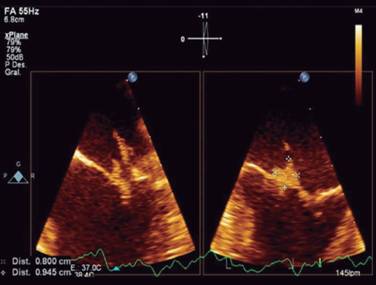

A 37-year-old man, previously healthy, with no history of contagious infectious disease and cardiovascular disease. He is from the State of Mexico, with history of intravenous opioids use (tramadol) 7 times per week, for chronic lower back pain secondary to lumbar herniated disc of one year of progress. The clinical condition started while he was driving, with sudden alteration of alertness manifested by disorientation, drowsiness and aphasia, their relatives observed it so that he was transferred to a private hospital. Upon admission, he remained disoriented. The physical examination is notable for a IV/VI holosystolic murmur over the apex radiating to the axilla. There were painful, nodular, erythematous, skin lesions localized in the pads of the fingers, as well as small, painless, flat spots, red to bluish red on the palms and soles [Osler’s nodes (Figure 1) and Janeway’s lesions (Figure 2)]. The rest of the physical and neurological examination did not present abnormalities. He was admitted to the Medical Center «20 de Noviembre» with fever of 38 oC, breathing rate of 24 rpm, heart rate of 115 bpm, blood pressure 100/60 mmHg. Fluid therapy and empirical antibiotic therapy were started (vancomycin and ceftriaxone). Initial laboratory test results with complete blood count indicating leukocytes of 23,000 mm3, platelets of 108,000 mm3, blood creatinine of 1.3 mg/dL, the rest remained unchanged. Blood cultures were negative. Cranial tomography (cranial CT) without evidence of areas of ischemia or hemorrhage. We proceeded to do a lumbar puncture and the cerebrospinal fluid (CSF) analysis showed cloudy fluid, glucose of 32 mg/dL, proteins of 165 mg/dL, leukocytes of 1760 and lymphocyte of 0. The CSF culture result was isolation of Staphylococcus aureus at 72 hours. The report of the transthoracic echocardiogram was: a structurally normal mitral valve, maximum gradient of 6 mmHg, medium gradient of 3 mmHg, with maximum velocity of 1.2 m/s, with a jet of severe regurgitation, reaching the left atrium roof. Maximum velocity of the jet of 4.4 m/s, with a suggestive image of a vegetation on the anterior leaflet. The transesophageal echocardiogram showed no thickened valves, with a vegetation of 1 × 0.9 cm-sized vegetation on the anterior leaflet, in segments 1 and 2, which oscillated during the cardiac cycle, with a filiform appendix adhered to the distal end of the vegetation (Figure 3), that affected the severe regurgitation jet which was visualized along the lateral wall of the atrium. Vital signs remained stable within the course; however, 72 hours after, he presented decreased alertness of less than 8 points of the Glasgow scale, with respiratory failure requiring advanced airway management and mechanical ventilation, entering the intensive care unit. Due to persistent hemodynamic instability and high-risk of embolism 5 days after entering, he required surgical intervention with valve replacement. He did not present post-surgical complications. Due to clinical state improvement, he was extubated 72 hours after surgical intervention, with no neurological sequela and without cardiac failure, data that might be frequent complications of this disease. Clinically this case meets the modified Duke criteria for clinically infective endocarditis due to the presence of vascular lesions and embolic phenomena, cultures with the presence of Staphylococcus aureus isolated from cerebrospinal fluid and the presence of a vegetation on the echocardiogram.